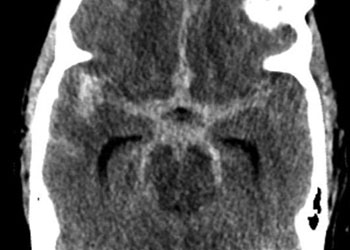

Endovascular:

Hydrocephalus and Brainstem Tumor

Author: Jonathan L. Brisman M.D., F.A.C.S., Read More!